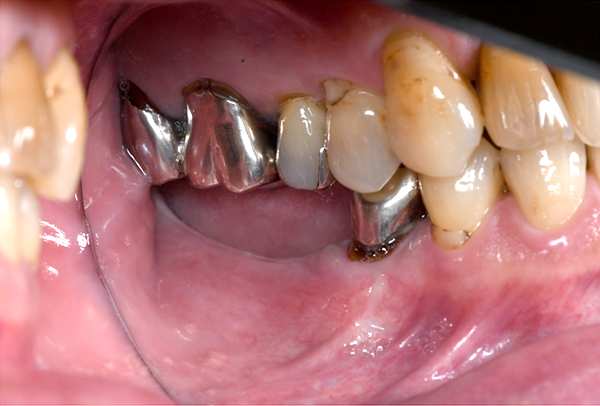

症例4. 歯冠長延長術

![]() |

| 歯平面が傾いてしまっています。 | 歯茎を下げる手術を行いました。 |